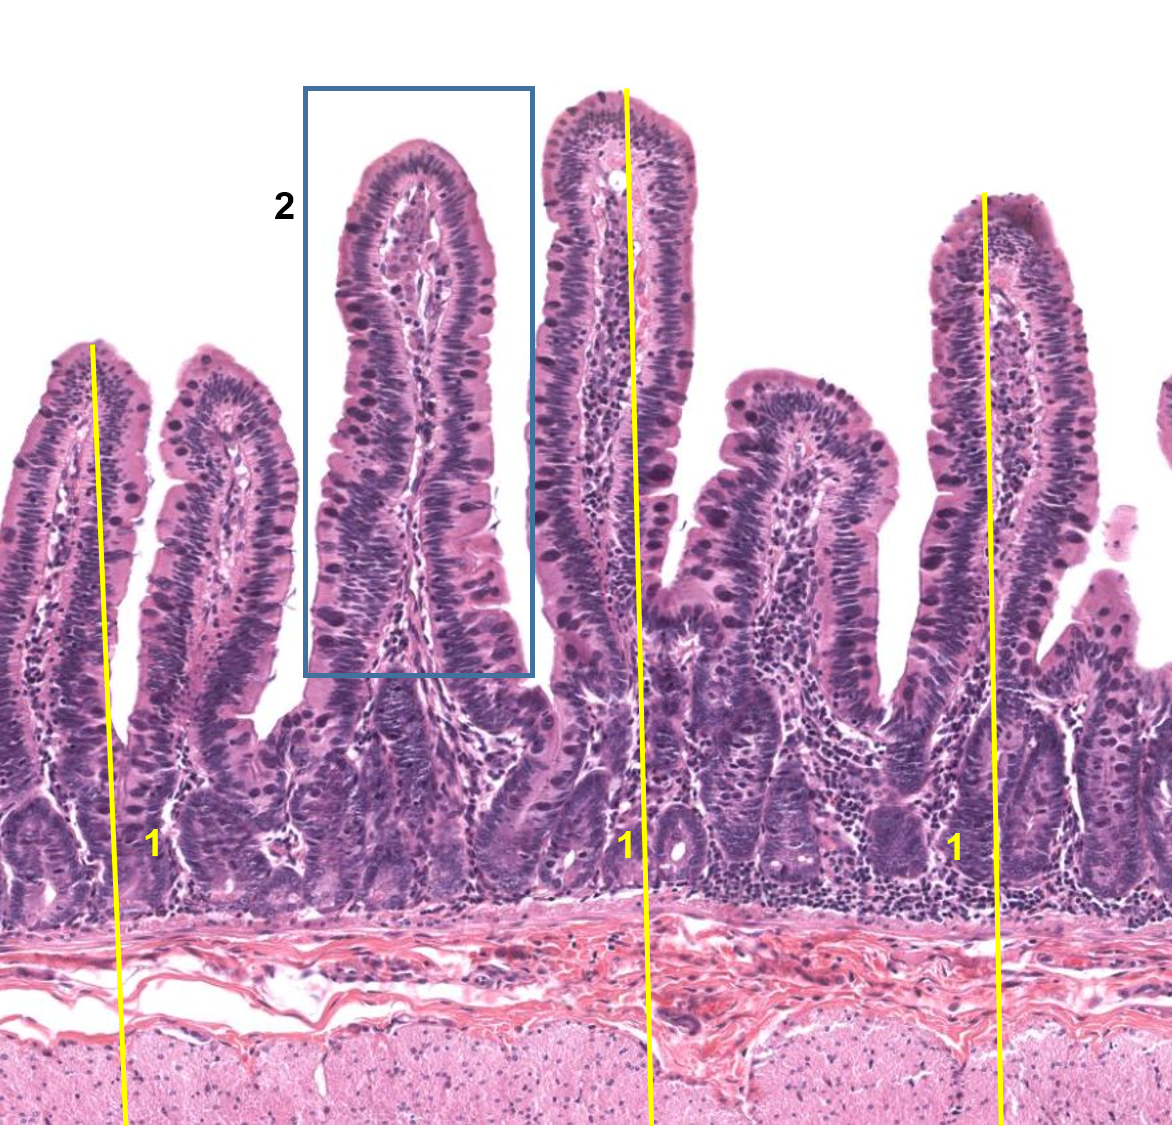

1: intestino delgado / Duodeno

2: Vilosidades